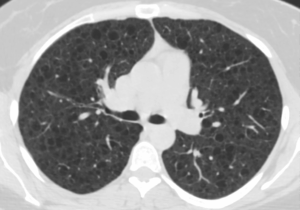

Image of lungs affected by Lymphangioleiomyomatosis (LAM) from The LAM Foundation.